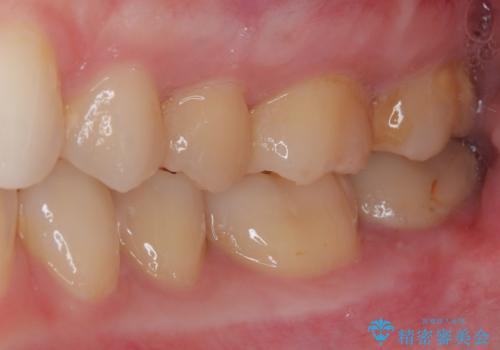

- 奥歯に激痛が走り近医を受診したところ、根管治療が必要とのことで、当院での治療を希望して来院された患者様です。

奥歯2歯の間からむし歯が広がったようで、最後方歯は既に神経が失活している状態で、手前の歯は神経組織に問題はないものの速やかに処置が必要な状態でした。

最後方歯は根管治療を行った上でオールセラミッククラウンにて補綴治療を行うこととし、手前の歯はセラミックインレーにて修復治療を行うこととしました。